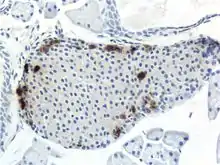

A pancreatic islet, stained.

A pancreatic islet, stained. A pancreatic islet, showing alpha cells

A pancreatic islet, showing alpha cells A pancreatic islet, showing beta cells.

A pancreatic islet, showing beta cells.